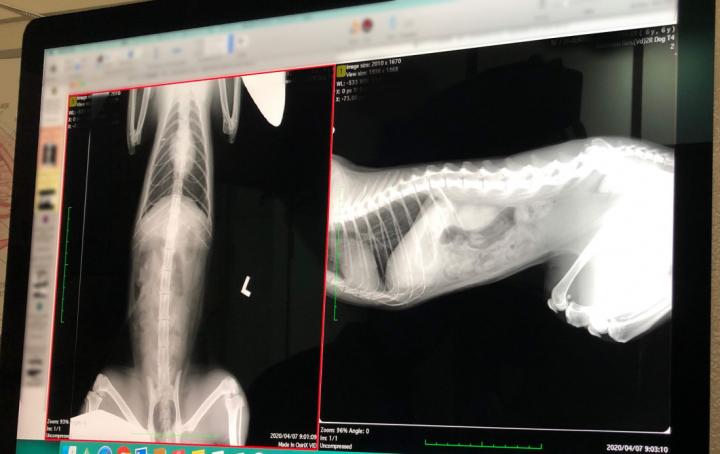

で、レントゲンの方ですが・・・

どうも肝臓が少し小さいみたい、とのこと。

あまり小さいと(小肝症)色々問題??なのかな?というイメージが、自分でネットで色々調べてうっすらあったのできいてみたのですが、まぁ問題はなさそう。

寿命にも影響ないですか…?と、怖々きいてみましたが大丈夫でしょう、との事。

痩せた猫だと小さく映りがち?みたいなことも仰ってました。

エコーも問題無し。腫瘍とかも無かったようです(ほっ)。

やっぱり肝臓小さいね~みたいな事は言ってましたが…。